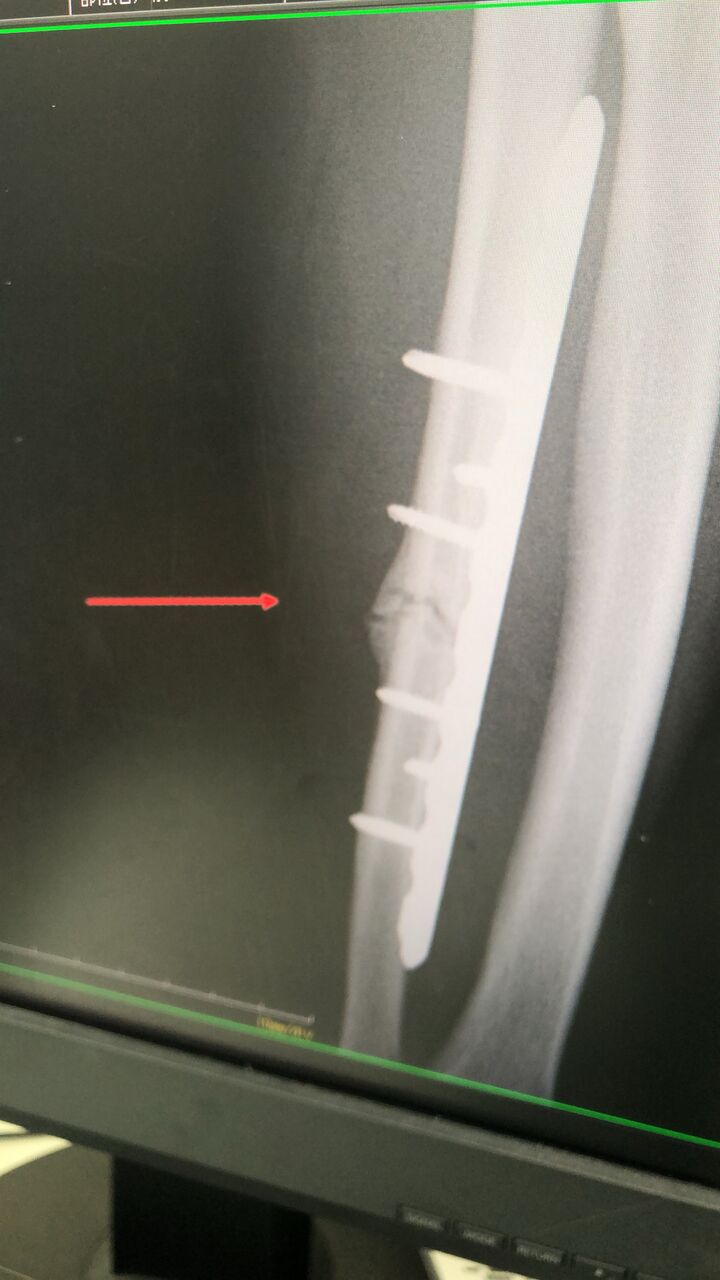

リング 試合で打撃をうけ、左の前腕を

骨折しました、

他院で、手術後に、なかなか良くならず

当院に相談に行きました

9A8E950A-8616-4177-B0ED-7E62F235273A

肩から手関節をほぐし、超音波骨治療器及びテーピングで対応していきます

回復していくと思います